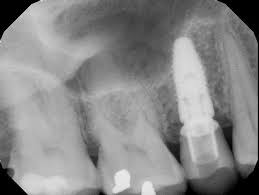

3. What option can be selected regarding the implant seen in this X ray?